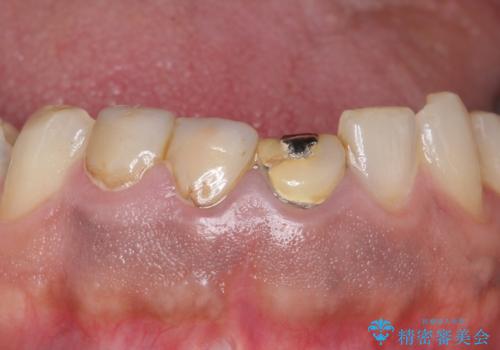

- 歯がない左側でものが咬めず、右側で咬むと歯が痛むので診て欲しいといらっしゃった方の症例です。

根尖病変が認められる歯は再根管治療を行い、歯根が破折していた左上4は抜歯しました。

インプラントは希望されなかったため、左側は1番から7番のロングスパンブリッジによる補綴を行いました。